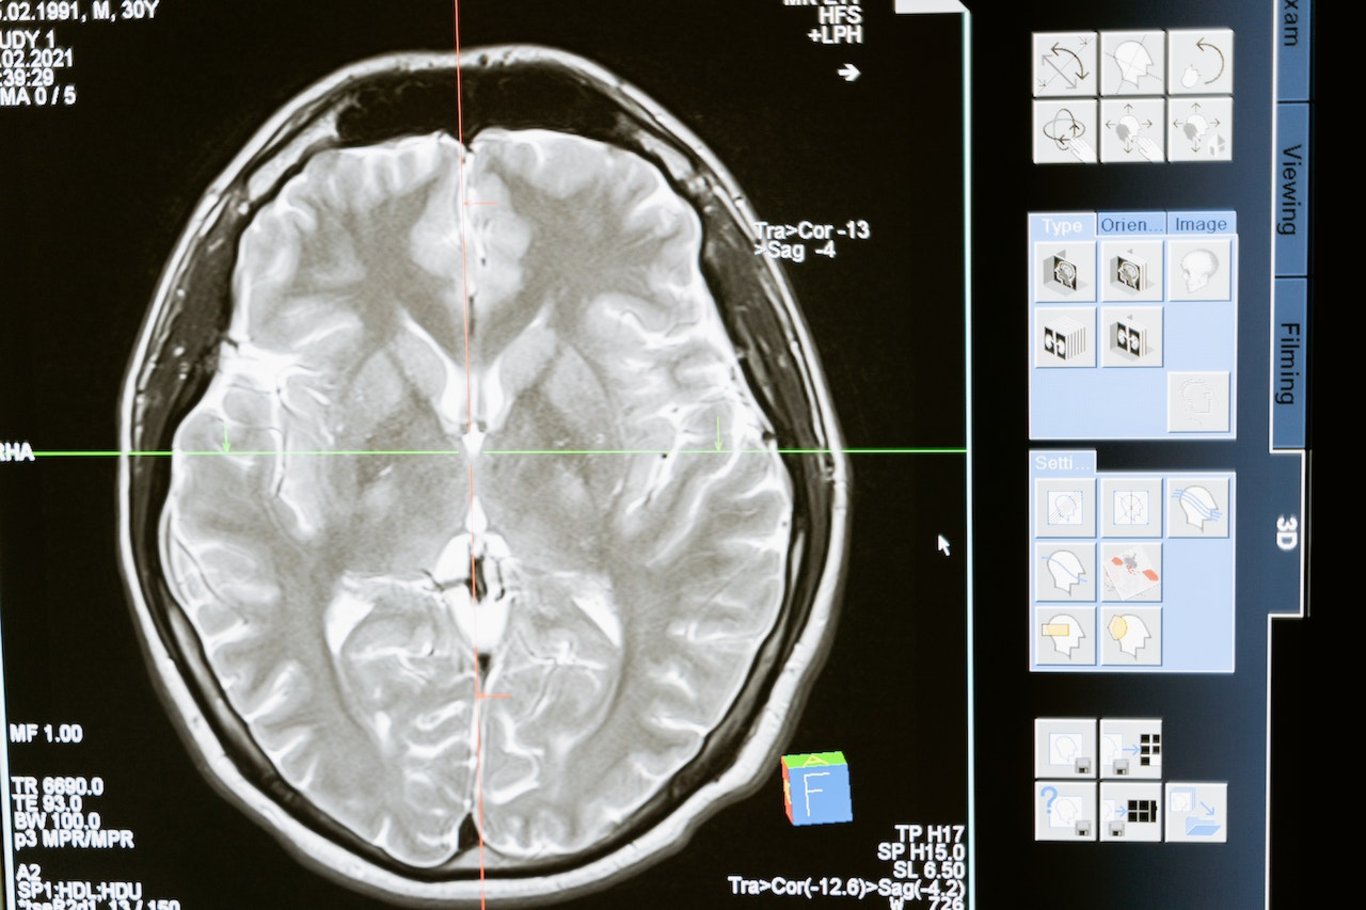

2006 senesinde çekilen beyin tomogrofileri, Price’ın beynindeki iki düzineden fazla alanın sıradandan daha büyük olduğunu ortaya çıkardı. Bunun ne anlama geldiği hâlâ ucu sarih bir sualdir.